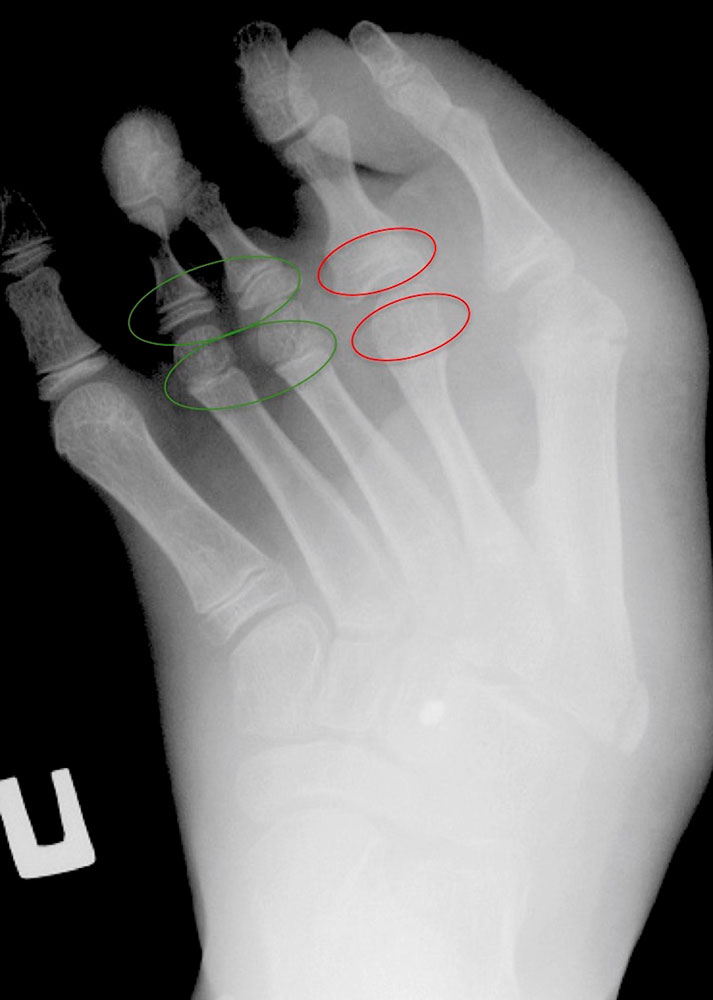

Temporäre Epiphysiodesen werden durch das vorübergehende Einsetzen von Implantaten im Bereich der Wachstumsfugen erreicht, die nach einer bestimmten Zeit wieder entfernt werden können. Obwohl es etliche Implantate für diese Operation gibt, haben sie alle das gleiche Prinzip, bei dem die Wachstumsfuge fest überbrückt („geklammert“) und dadurch im Wachstum gehemmt wird .